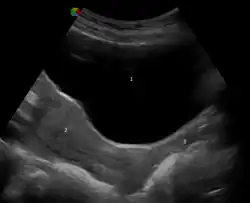

When not sexually aroused, the vagina is a collapsed tube, with the front and back walls placed together. The lateral walls, especially their middle area, are relatively more rigid. Because of this, the collapsed vagina has an H-shaped cross section.[10][14] Behind, the upper vagina is separated from the rectum by the recto-uterine pouch, the middle vagina by loose connective tissue, and the lower vagina by the perineal body.[15] Where the vaginal lumen surrounds the cervix of the uterus, it is divided into four continuous regions (vaginal fornices); these are the anterior, posterior, right lateral, and left lateral fornices.[9][10] The posterior fornix is deeper than the anterior fornix.[10]